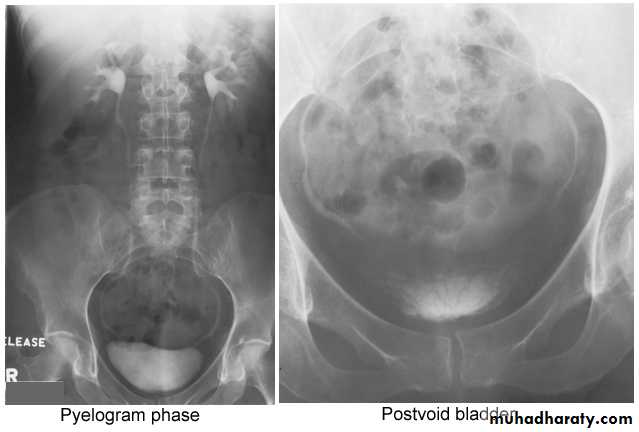

2. Pyelogram Phase(l-5 minutes after injection of contrast) .3. After 10 minutes with compression, to get better distention of the pelvis and calyces.

4. Full length film after release of compression .

5. A full bladder film (with the urinary bladder fully distended with contrast)

6. Post voiding full length film